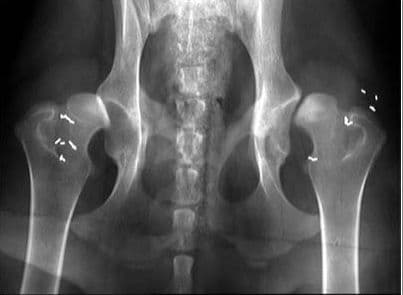

Bệnh viêm khớp háng thường khởi phát rất đột ngột. Biểu hiện của bệnh là sốt nhẹ hoặc sốt cao, đau nhức ở vùng đùi hoặc đầu gối, cử động háng khó khăn, đau nhức khiến người bệnh đi lại khập khiễng… Trường hợp bệnh nặng khi chụp X-quang sẽ phát hiện tràn dịch trong khớp, giãn rộng khe khớp và đường mỡ quanh khớp bị nén lại. Viêm khớp háng kéo theo những cơn đau nhức rất dữ dội, ảnh hưởng đến sinh hoạt và cuộc sống của người bệnh. Do đó, việc chữa bệnh viêm khớp háng cần được thực hiện càng sớm càng tốt.

Các bác sĩ chuyên khoa cơ xương khớp cho biết, chụp X- quang hoặc chụp MRI để xác định mức độ bệnh viêm khớp háng là cách giúp điều trị bệnh tốt nhất. Căn cứ trên kết quả chụp, các bác sĩ sẽ có những tư vấn và chỉ định phương pháp điều trị phù hợp nhất cho bệnh nhân.